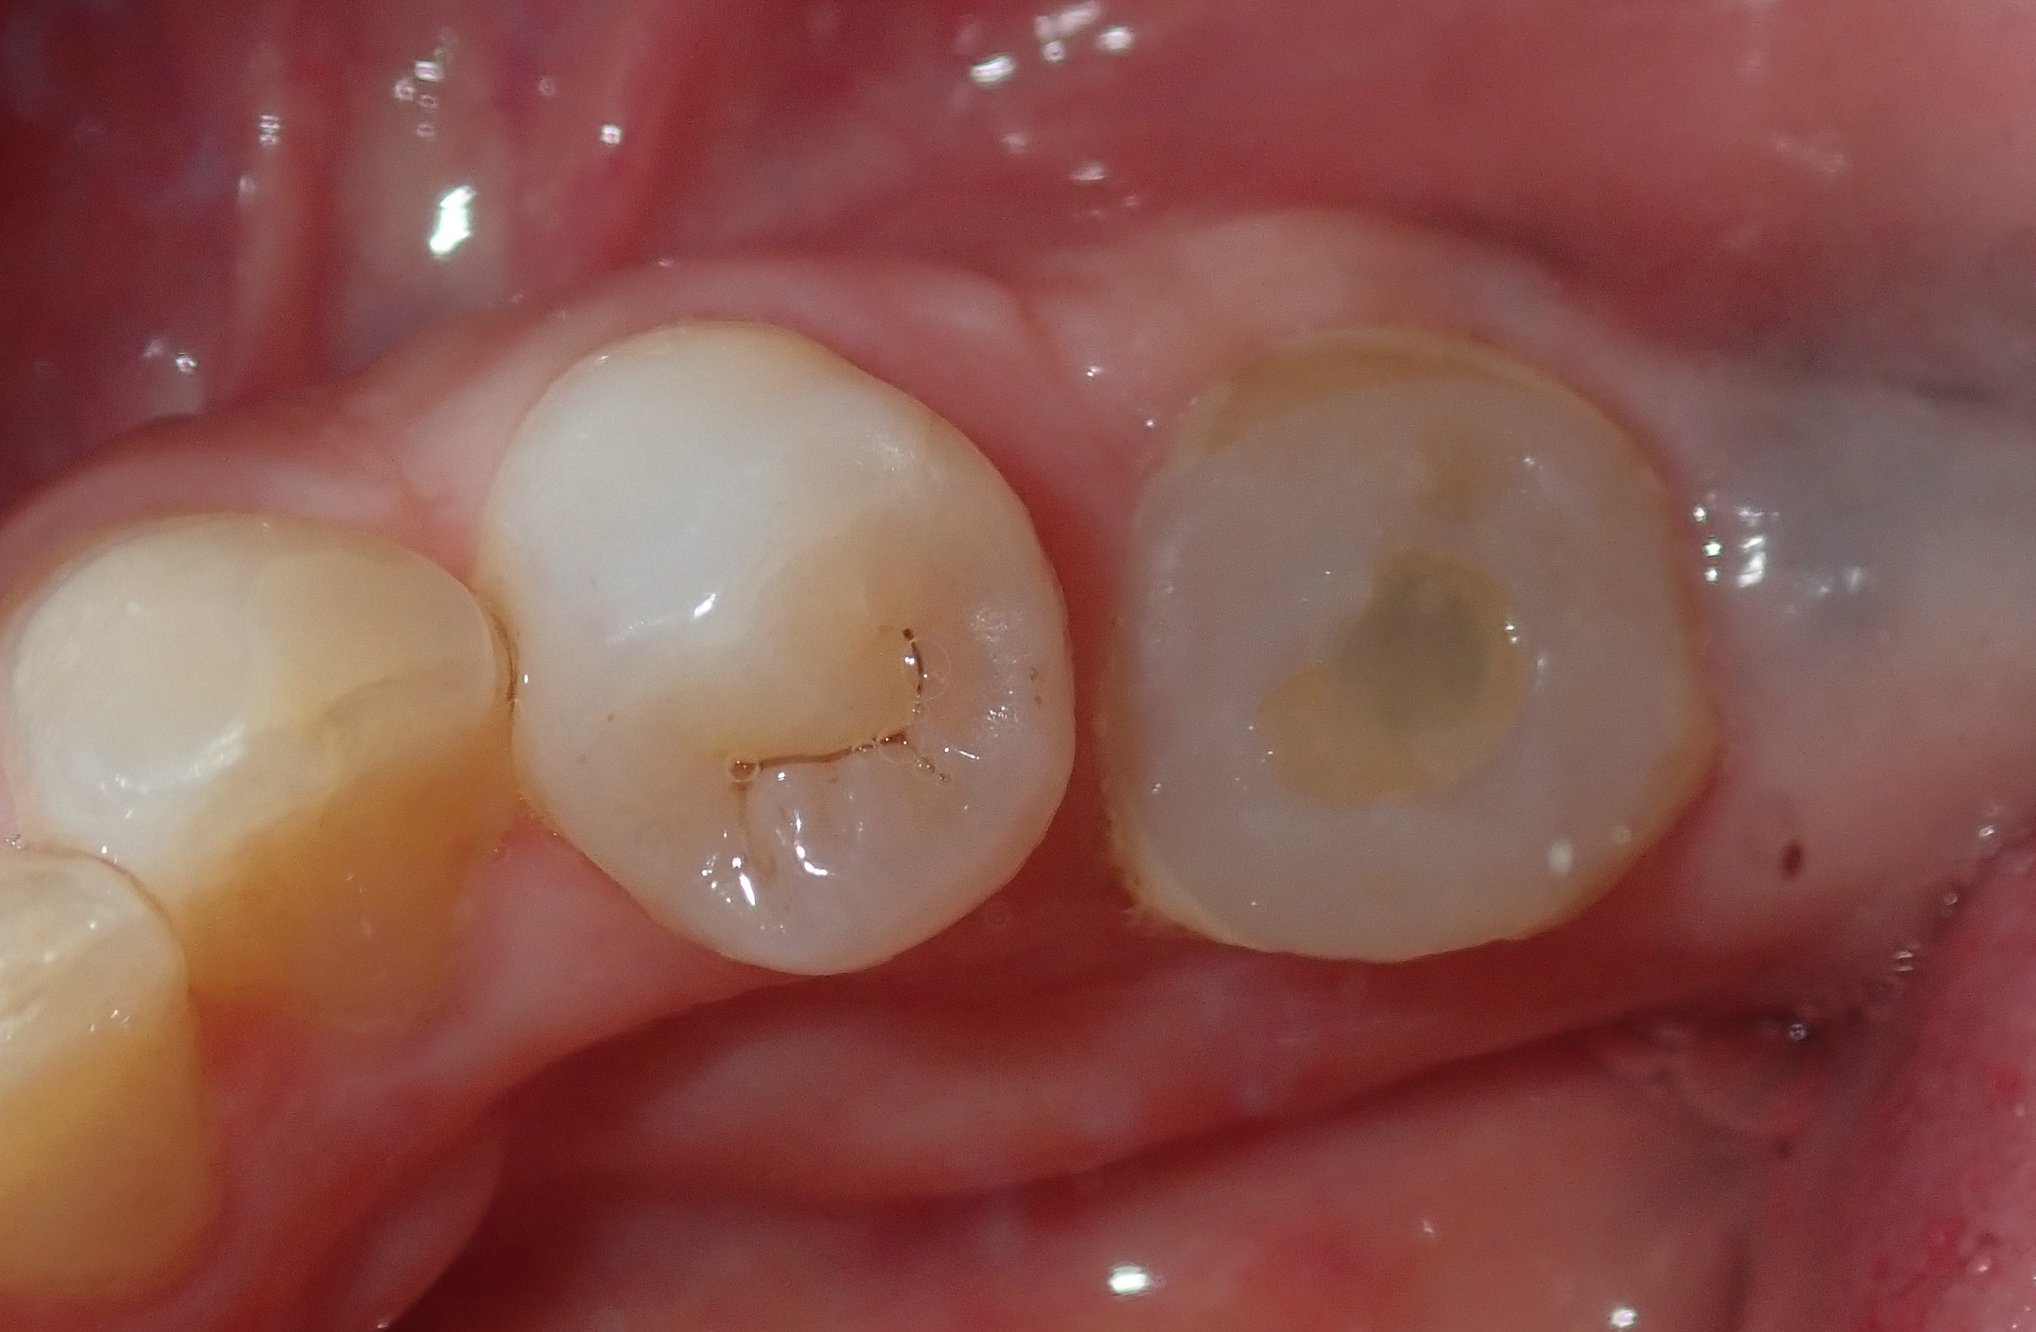

Fig 9. After removal of the custom healing abutment, a natural-appearing emergence profile for a mandibular molar, square in cross-section, was evident.

Figure 9

A 5 mm x 10 mm implant (MIS® V3, MIS Implants, mis-implants.com) had been placed at the mandibular first molar site and was ready for restoration. At the uncovering, a custom healing abutment that had been fabricated using an emergence profile management system (Cervico System, VP Innovato Holdings Ltd, vpicervico.com) to match the emergence profile of a mandibular molar was inserted into the integrated implant, and the soft tissue was sutured around the abutment (Figure 8). After several weeks to allow the soft tissue to heal, the restoration phase began. The custom healing abutment was removed, revealing healthy soft tissue with an emergence cross-section that was relatively square, mimicking a molar (Figure 9).

To avoid potential soft tissue collapse when the impression was captured, a custom impression abutment was created to support the soft tissue and properly communicate to the laboratory technician what had developed intraorally (Figure 10). This technique may be used with either open-tray or closed-tray impression abutments. The impression was taken and the custom healing abutment was reinserted intraorally while the laboratory constructed the restoration. The completed restoration was returned, the custom healing abutment was removed, and the implant restoration was inserted. The result was an emergence profile that mimicked a natural molar, enabling natural-looking esthetics (Figure 11). A radiograph demonstrated a smooth transition emanating from the implant platform to support an emergence profile that allowed soft-tissue maintenance and helped to eliminate potential food traps (Figure 12).